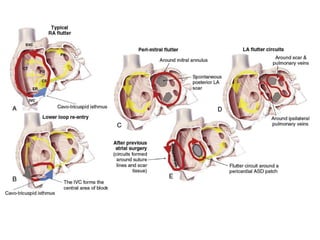

CAVO-TRICUSPID ISTHMUS DEPENDENT FLUTTER.

Typical flutter is as a macroreentrant circuit within the

right atrium. It can be considered to be a broad activation

wavefront rotating between the tricuspid annulus (TA)

anteriorly and the crista terminalis-eustachian

ridge/inferior vena cava (IVC) posteriorly .

In the most common form (approximately 90%) the circuit

Non Cavo-Tricuspid Isthmus–Dependent Flutter

(Atypical Atrial Flutter).

 Atypical flutter may occur primarily in the right or the left

atrium.

 When the V1 flutter wave is deeply inverted, this is highly

likely to represent a right atrial circuit. Conversely, when

the V1 flutter wave is upright, this generally indicates an

LA circuit.

However, many variations exist and these

findings lack sensitivity and specificity.

 The atrial rate in atypical flutter has wide limits (120 to

300 bpm) depending on the underlying circuit and

pathology).

The pathology underlying atypical flutter is highly variable, and

these circuits may occur in the context of

(1) Prior corrective atrial surgery (congenital heart disease [CHD],

valvular heart disease, after a Maze procedure or cardiac

transplantation),

(2) Previous AF ablation,

(3) Advanced atrial disease associated with atrial enlargement

(these patients frequently have underlying pathologies such as

heart failure [systolic or diastolic] or unoperated valvular heart

disease such as severe mitral regurgitation),

(4) In patients with normal atrial size and without an obvious

underlying pathologic condition. In these patients, spontaneous

scarring of unknown cause may be found at the time of atrial

mapping. These circuits have particularly been described in the RA

free wall.

The circuits involved in atypical (non–isthmus dependent)

AFL are highly variable and involve a range of anatomic

boundaries.

 These might be anatomic structures, surgical scars, or

regions of low voltage and slowed conduction.

 Stereotypical anatomic locations associated with certain

underlying pathologic conditions or procedures have been

defined.

 These include surgical repair of complex CHD such as

Mustard or Senning repair, Fontan repair, or simpler atrial

surgeries such as atrial septal defect (ASD) repair ,Mitral

valve surgery (repair or replacement).

Dual-loop or figure-of-8 reentry has been described

when there are two simultaneous circuits. This may occur

in either the left atrium (31 In patients with prior atrial

surgery, circuits particularly involve atriotomy scars. In

patients with prior LA ablation, circuits may be around the

pulmonary veins (roof dependent) or around the mitral

annulus (mitral isthmus dependent).